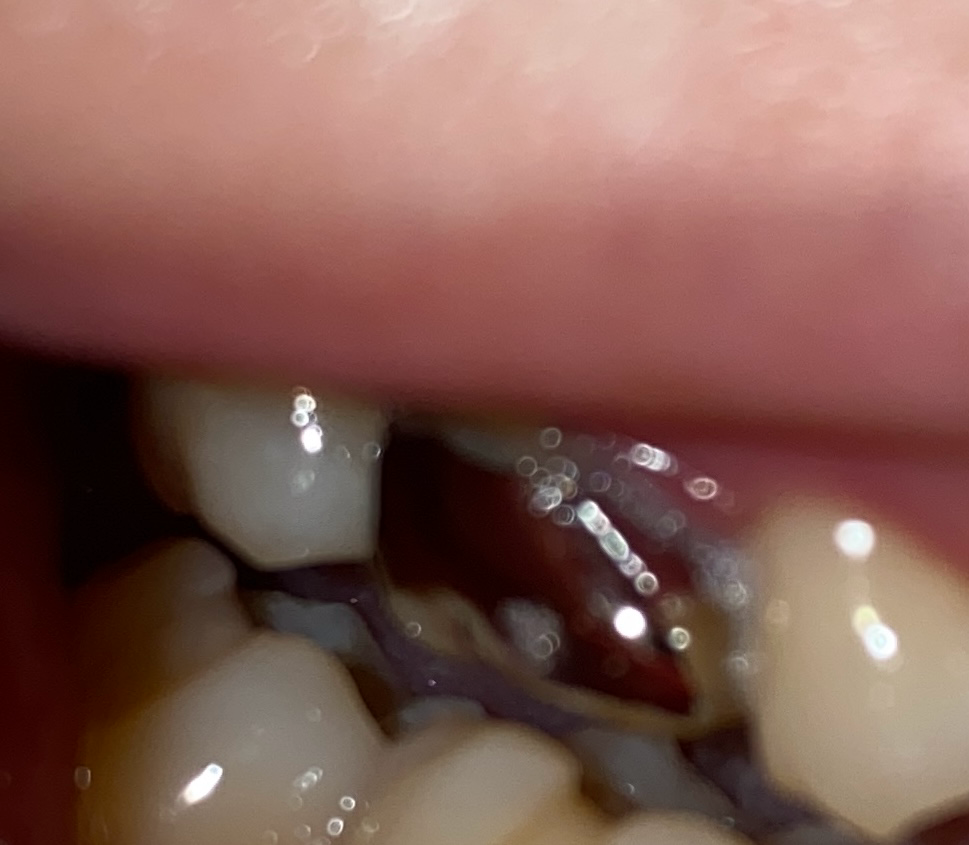

크라운 떨어졌는데 까만이는 무엇인가요?

크라운이 떨어지기 한달전부터 악취가 심했고 원래 이와 크라운 사이에 금이가서 그 사이가 치실을 넣으면 들어갈 정도로 벌어져있었습니다. 그리고 크라운과 이어진 이는 까만게 보였었구요.

• 1번 째 사진

치아 표면의 검은색은 착색, 이차충치 또는 시멘트가 변색된 것일 수 있습니다. 크라운 내부의 검은색은 시멘트가 변색되고 성분이 변해 그렇게 된 것이 맞습니다. 일단 잔여 시멘트를 잘 제거하고 다시 붙였다면 크게 문제 없는 진료로 생각됩니다.

안쪽에 보이는건 보철물을 붙히는 접착제가 오래되면 저렇게 까맣게 변색이 되는겁니다. 제거후에 다시 접착제를 도포해서 붙히시면됩니다.

사진으로 봤을 경우에는 크라운 내부의 시멘트가 용해되고 빈공간에 이물질이 들어간것으로 보입니다.

보철물을 부착할때는 내부의 이물질은 깨끗하게 제거하고 부착하기 때문에 탈락시에 해당물질이 있다면 부착을 하고 생겼을 가능성이 높습니다.